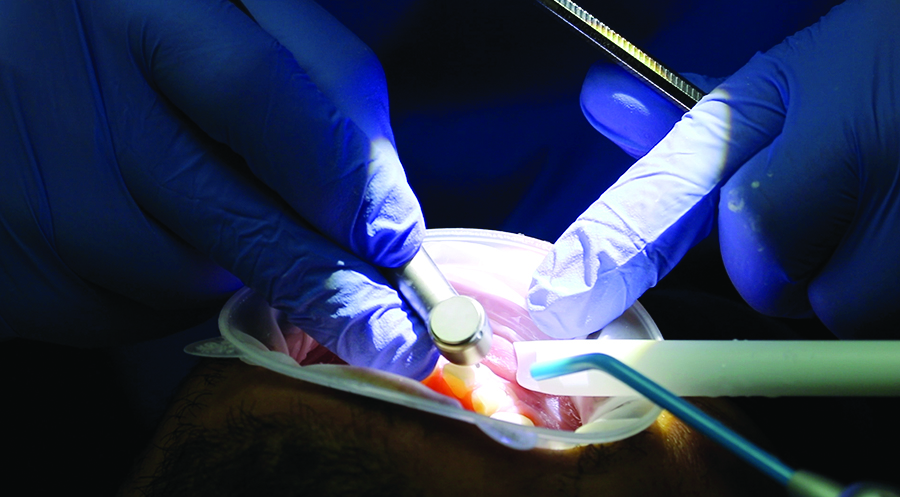

Fig. 8B

Placing the putty in the mouth.

Fig. 8C

Hardening of the mock-up.